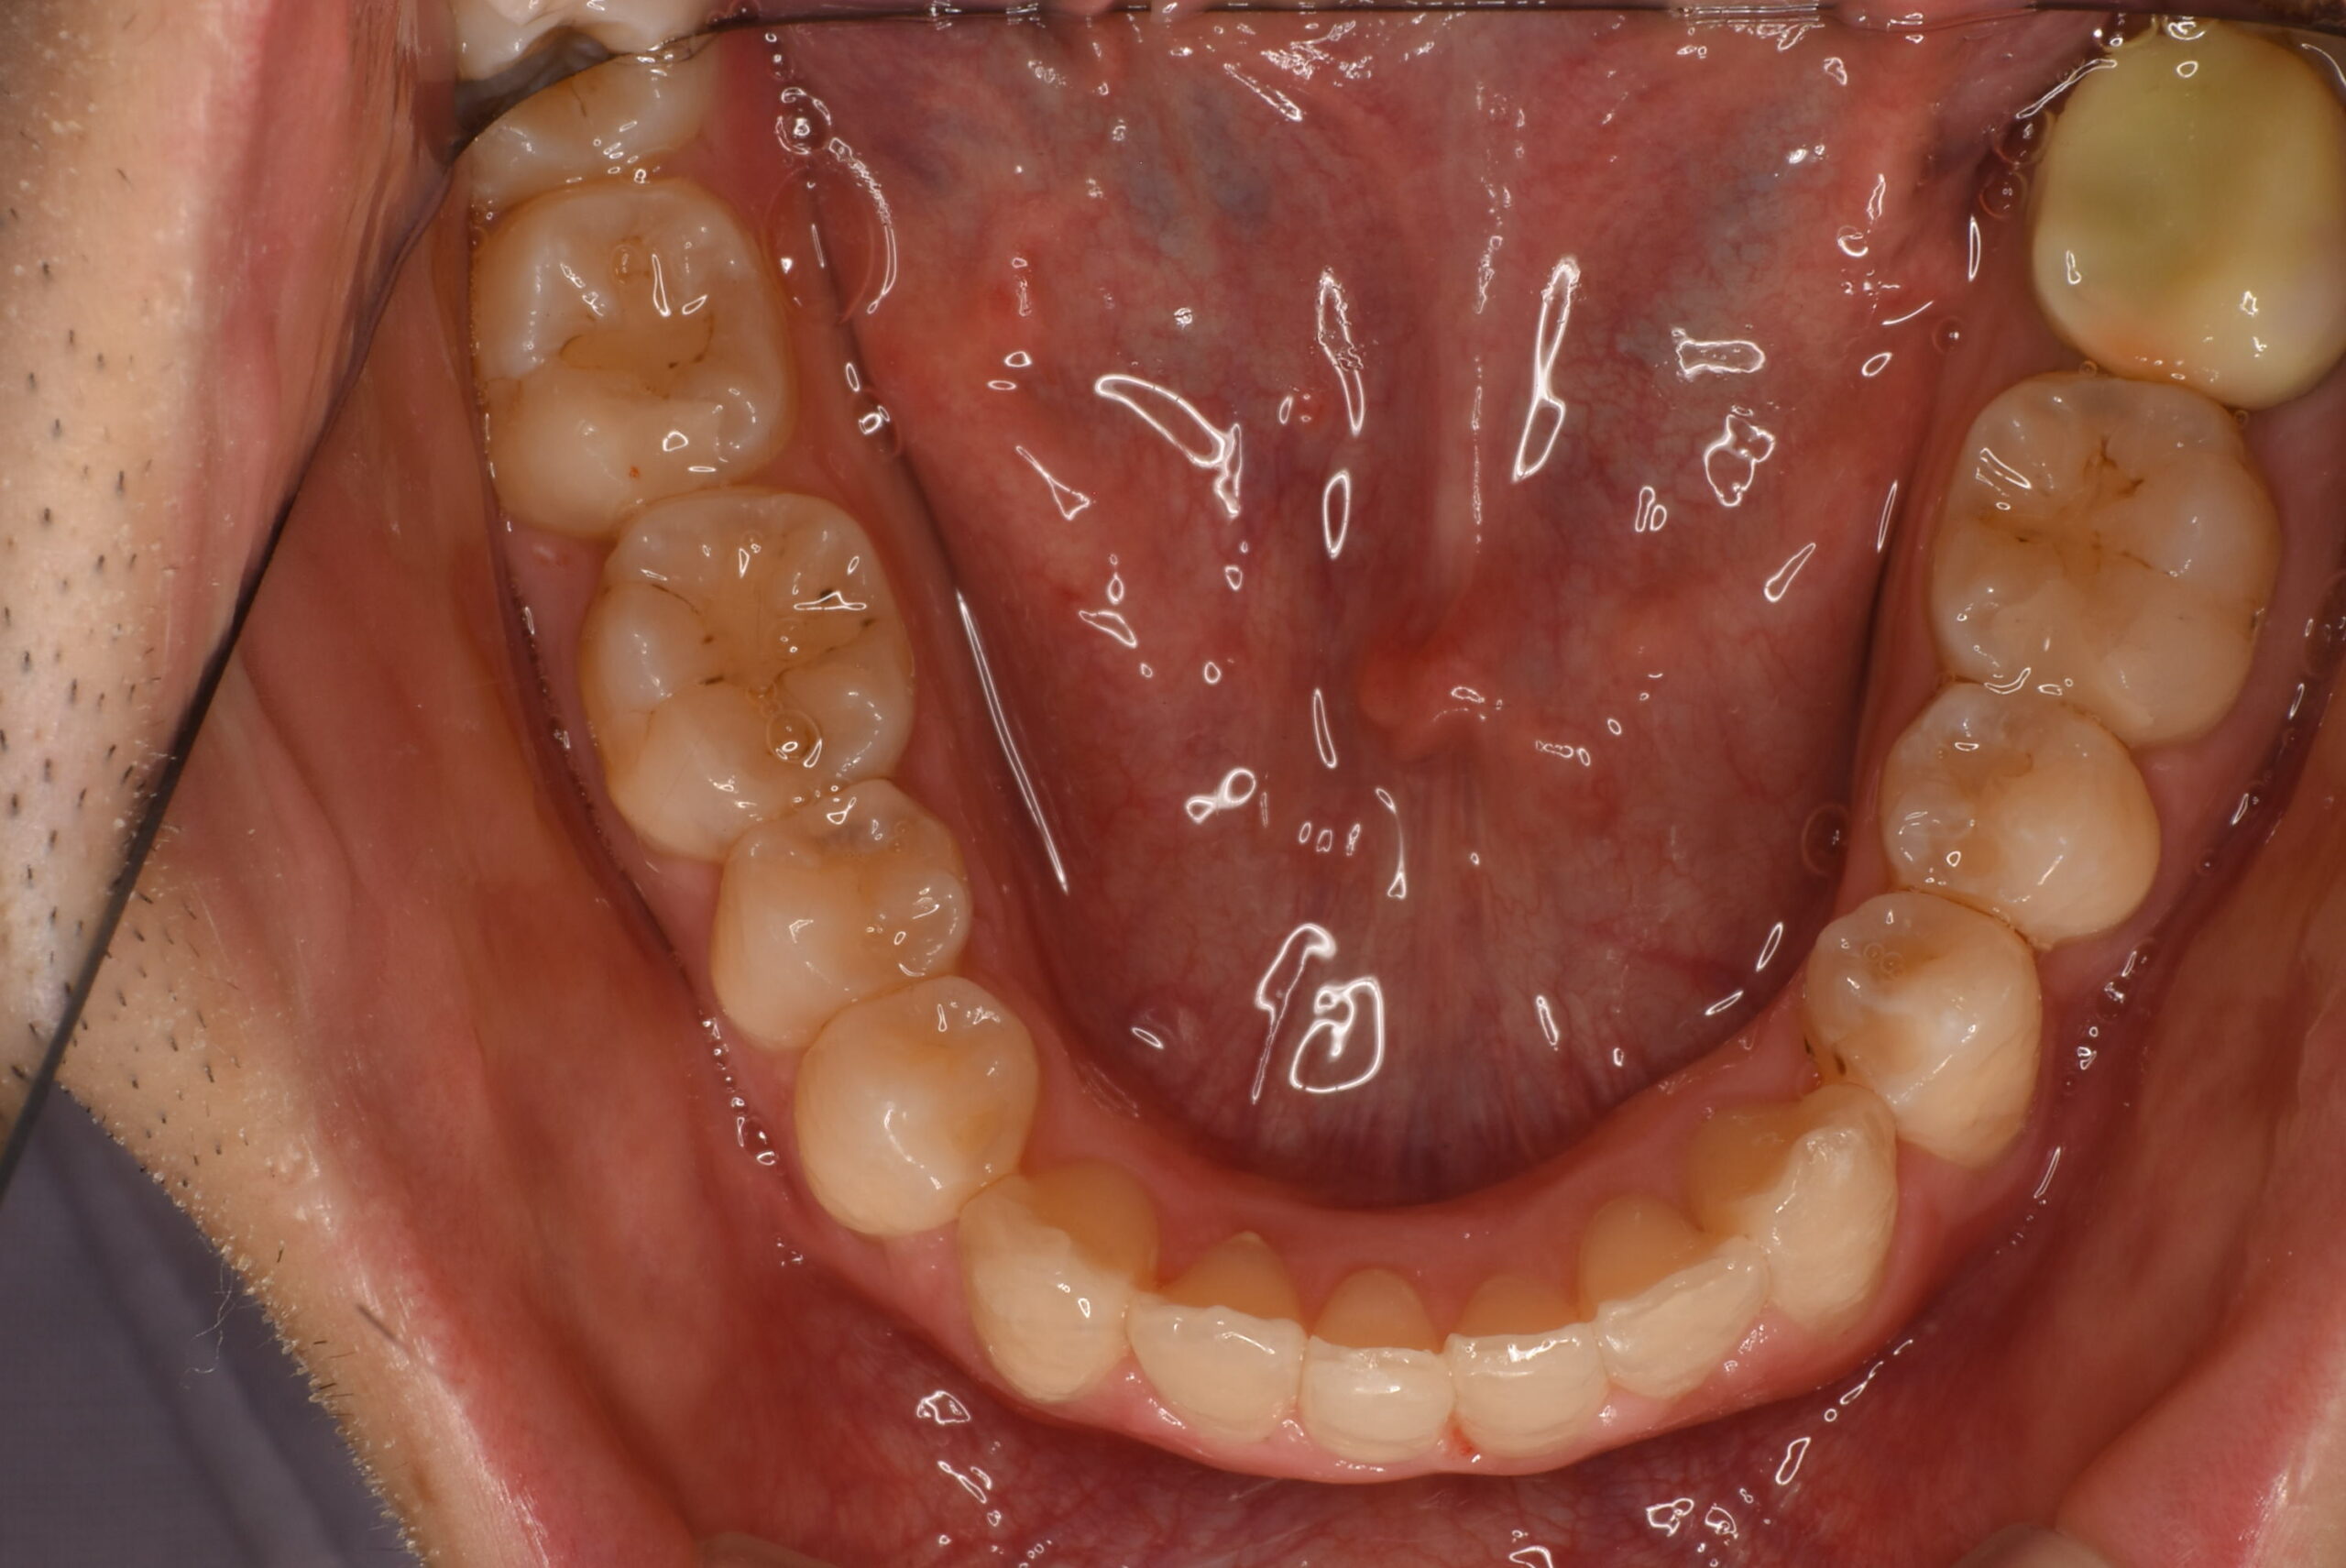

治療後_下顎咬合面